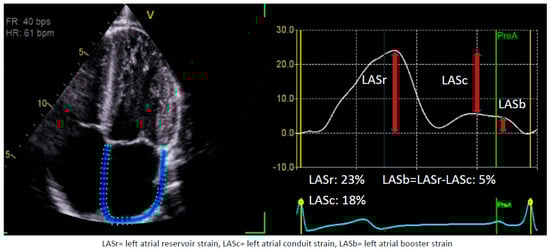

1.1. Assessment of LA Strain